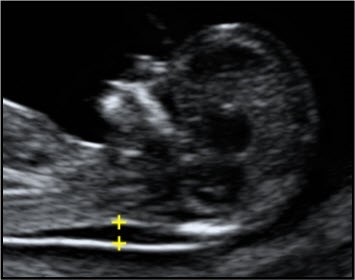

Criteria for measurement of the fetal crown rump length (CRL) as part of the combined 1st trimester screening programme

The CRL range should be between 45.0 and 84.0 mm.

The magnification of the fetus should be as large as possible clearly demonstrating the entire crown-rump length.

A midline sagittal section of the whole fetus should be obtained with the fetus horizontal on the screen, either supine or prone. The fetus should be in a neutral position with fluid visible between the fetal chin and chest, neither hyper extended nor flexed.

The best of three measurements should be taken. Linear callipers should be used to measure the maximum un-flexed length. Intersection of the callipers (+) should be placed on the outer margin of the skin borders of the CRL. Two images of the measured CRL must be retained, one for the patient record and one for audit purposes.